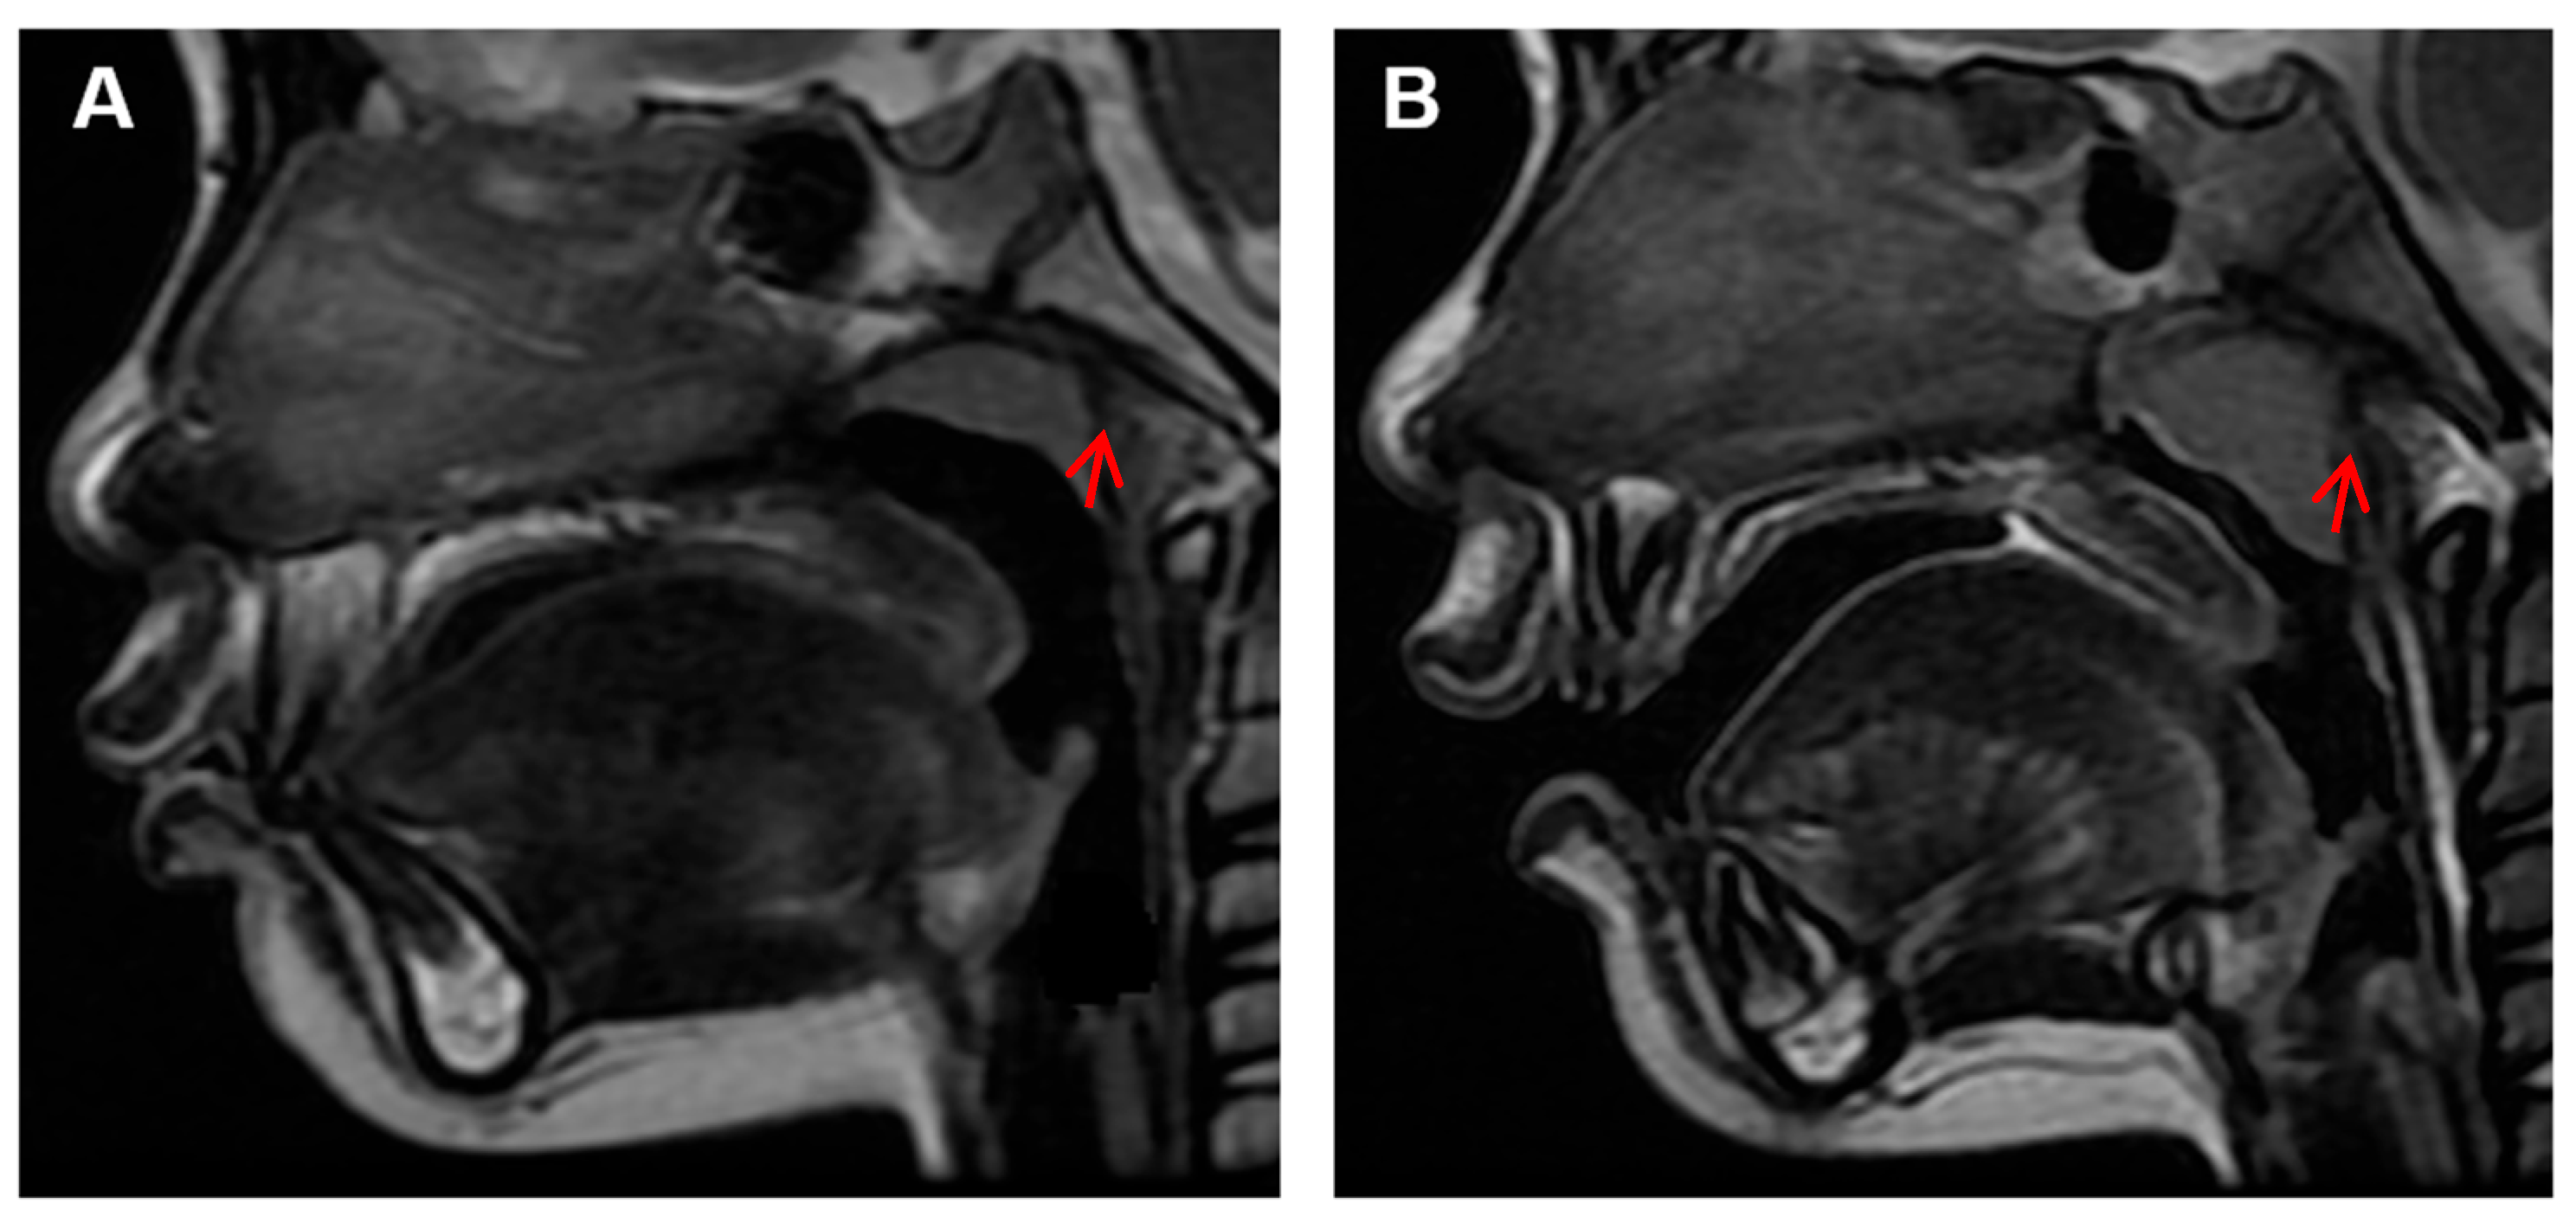

Figure 5.

MRI Images of normal and hypertrophic adenoids. (A) The red arrow indicates a normal adenoid; (B) The red arrow indicates a hypertrophic adenoid.